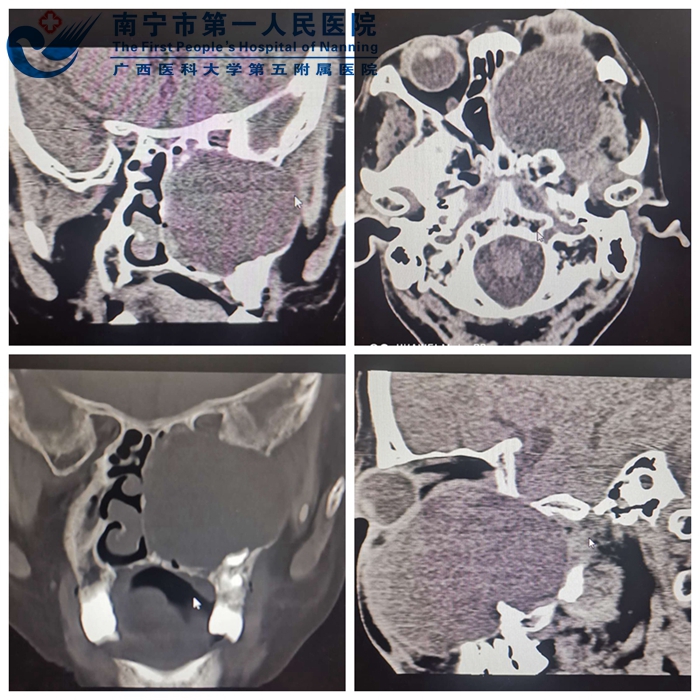

患者为一57岁女性,因左侧眶部、面颊部肿痛伴复视、视力下降1月来诊。患者入院前曾在市内某医院就诊,经CT检查提示“左上颌窦肿瘤”,因医疗条件所限,而转至我院。患者入院后,经复查眼眶、上颌骨CT,诊断为左侧上颌骨含牙囊肿,肿瘤已致上颌骨、眶骨、前颅底、颅中窝等多个解剖部位骨质破坏吸收及左眼球及视神经受压移位,致视力下降,为了予患者行肿瘤切除、解除视神经及眼球压迫的同时,为患者施行眶骨、上颌骨的一期修复重建,在影像科毛一朴主任的协助下,为患者进行CT骨三维重建,并将CT原始数据采集上传至能进行3D打印的公司,为患者施行量身打造个性数字化的三维钛网设计,经过三天的等待,请眼科等相关科室会诊,并与患者及家属的充分沟通,於昨天上午在科室主任韦理直副主任医师的主导下为患者成功的实施了手术。

1.术前CT影像资料1

2.术前CT影像资料2